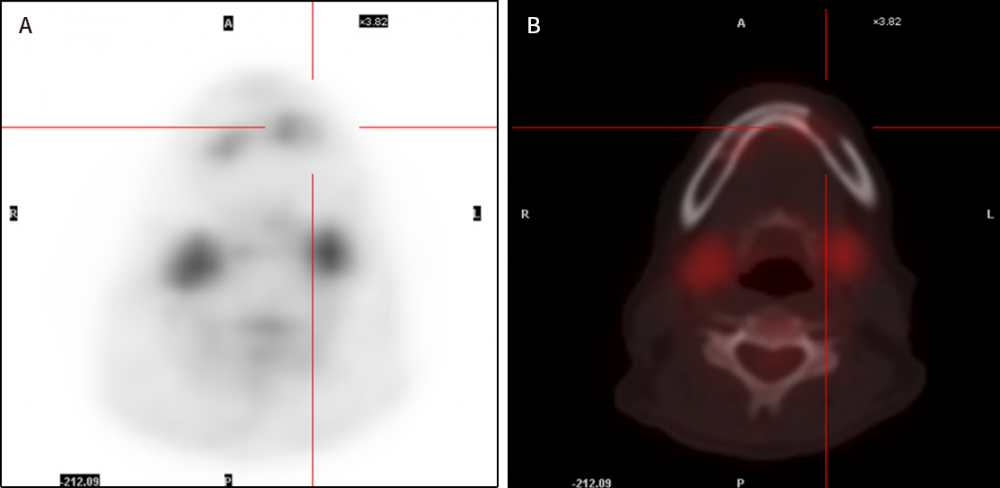

患者進行骨髓活檢,形態(tài)學檢查顯示紅系細胞百分比略高,鐵染色顯示鐵利用障礙。骨髓中可見少量噬血細胞。左下頜骨穿刺活檢并進行免疫組化檢測(圖 3),結(jié)果顯示瘤細胞 CD20(+),CD79a(+),Bc1-2(+),CD5(少量散在+),C-myc(少量+),Ki-67(+,90%),CD10(-),Kappa(-),Lambda(-),CD38(-),CD138(-),CD3(-),Desmin(-), MyoD1(-), Myogenin(-),CD99(-),CK(-),Syn(-),EMA(-),CyclinD1(-),Bc1-6(-),MUM1(-),CD30(-),SOX11(-),提示為惡性 B 細胞淋巴瘤(彌漫性大 B 細胞型)?;颊弑辉\斷為 DLBCL,轉(zhuǎn)入血液科進行免疫化療 [利妥昔單抗 600 mg d1,環(huán)磷酰胺 1.1 g d2,阿霉素 40 mg d2,長春地辛 4 mg d2,潑尼松 15 mg d1-5 (R-CHOP)]。R-CHOP 方案治療 5 個周期,患者再次進行全身 PET-CT 檢測,結(jié)果顯示左側(cè)下頜骨糖代謝下降(圖 4)。隨后進行輔助放療 15 次后,患者出院。在最近一次隨訪中,患者無發(fā)熱,無咳嗽,無腹痛,飲食正常,睡眠正常。

圖 4. 患者治療后 PET-CT 檢測結(jié)果